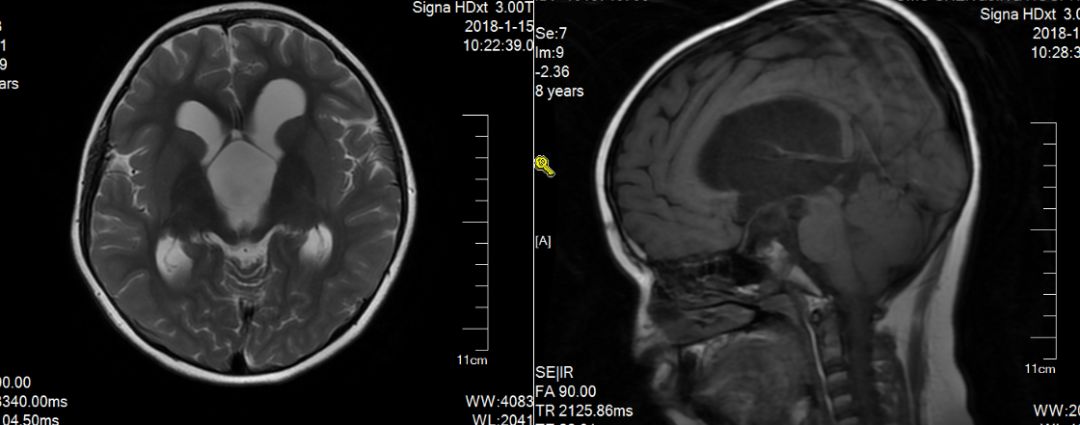

术后患儿情况:

目前患者恢复良好,偶有头痛,无颅内感染,无再发抽搐,出院后未服用抗癫痫药物。